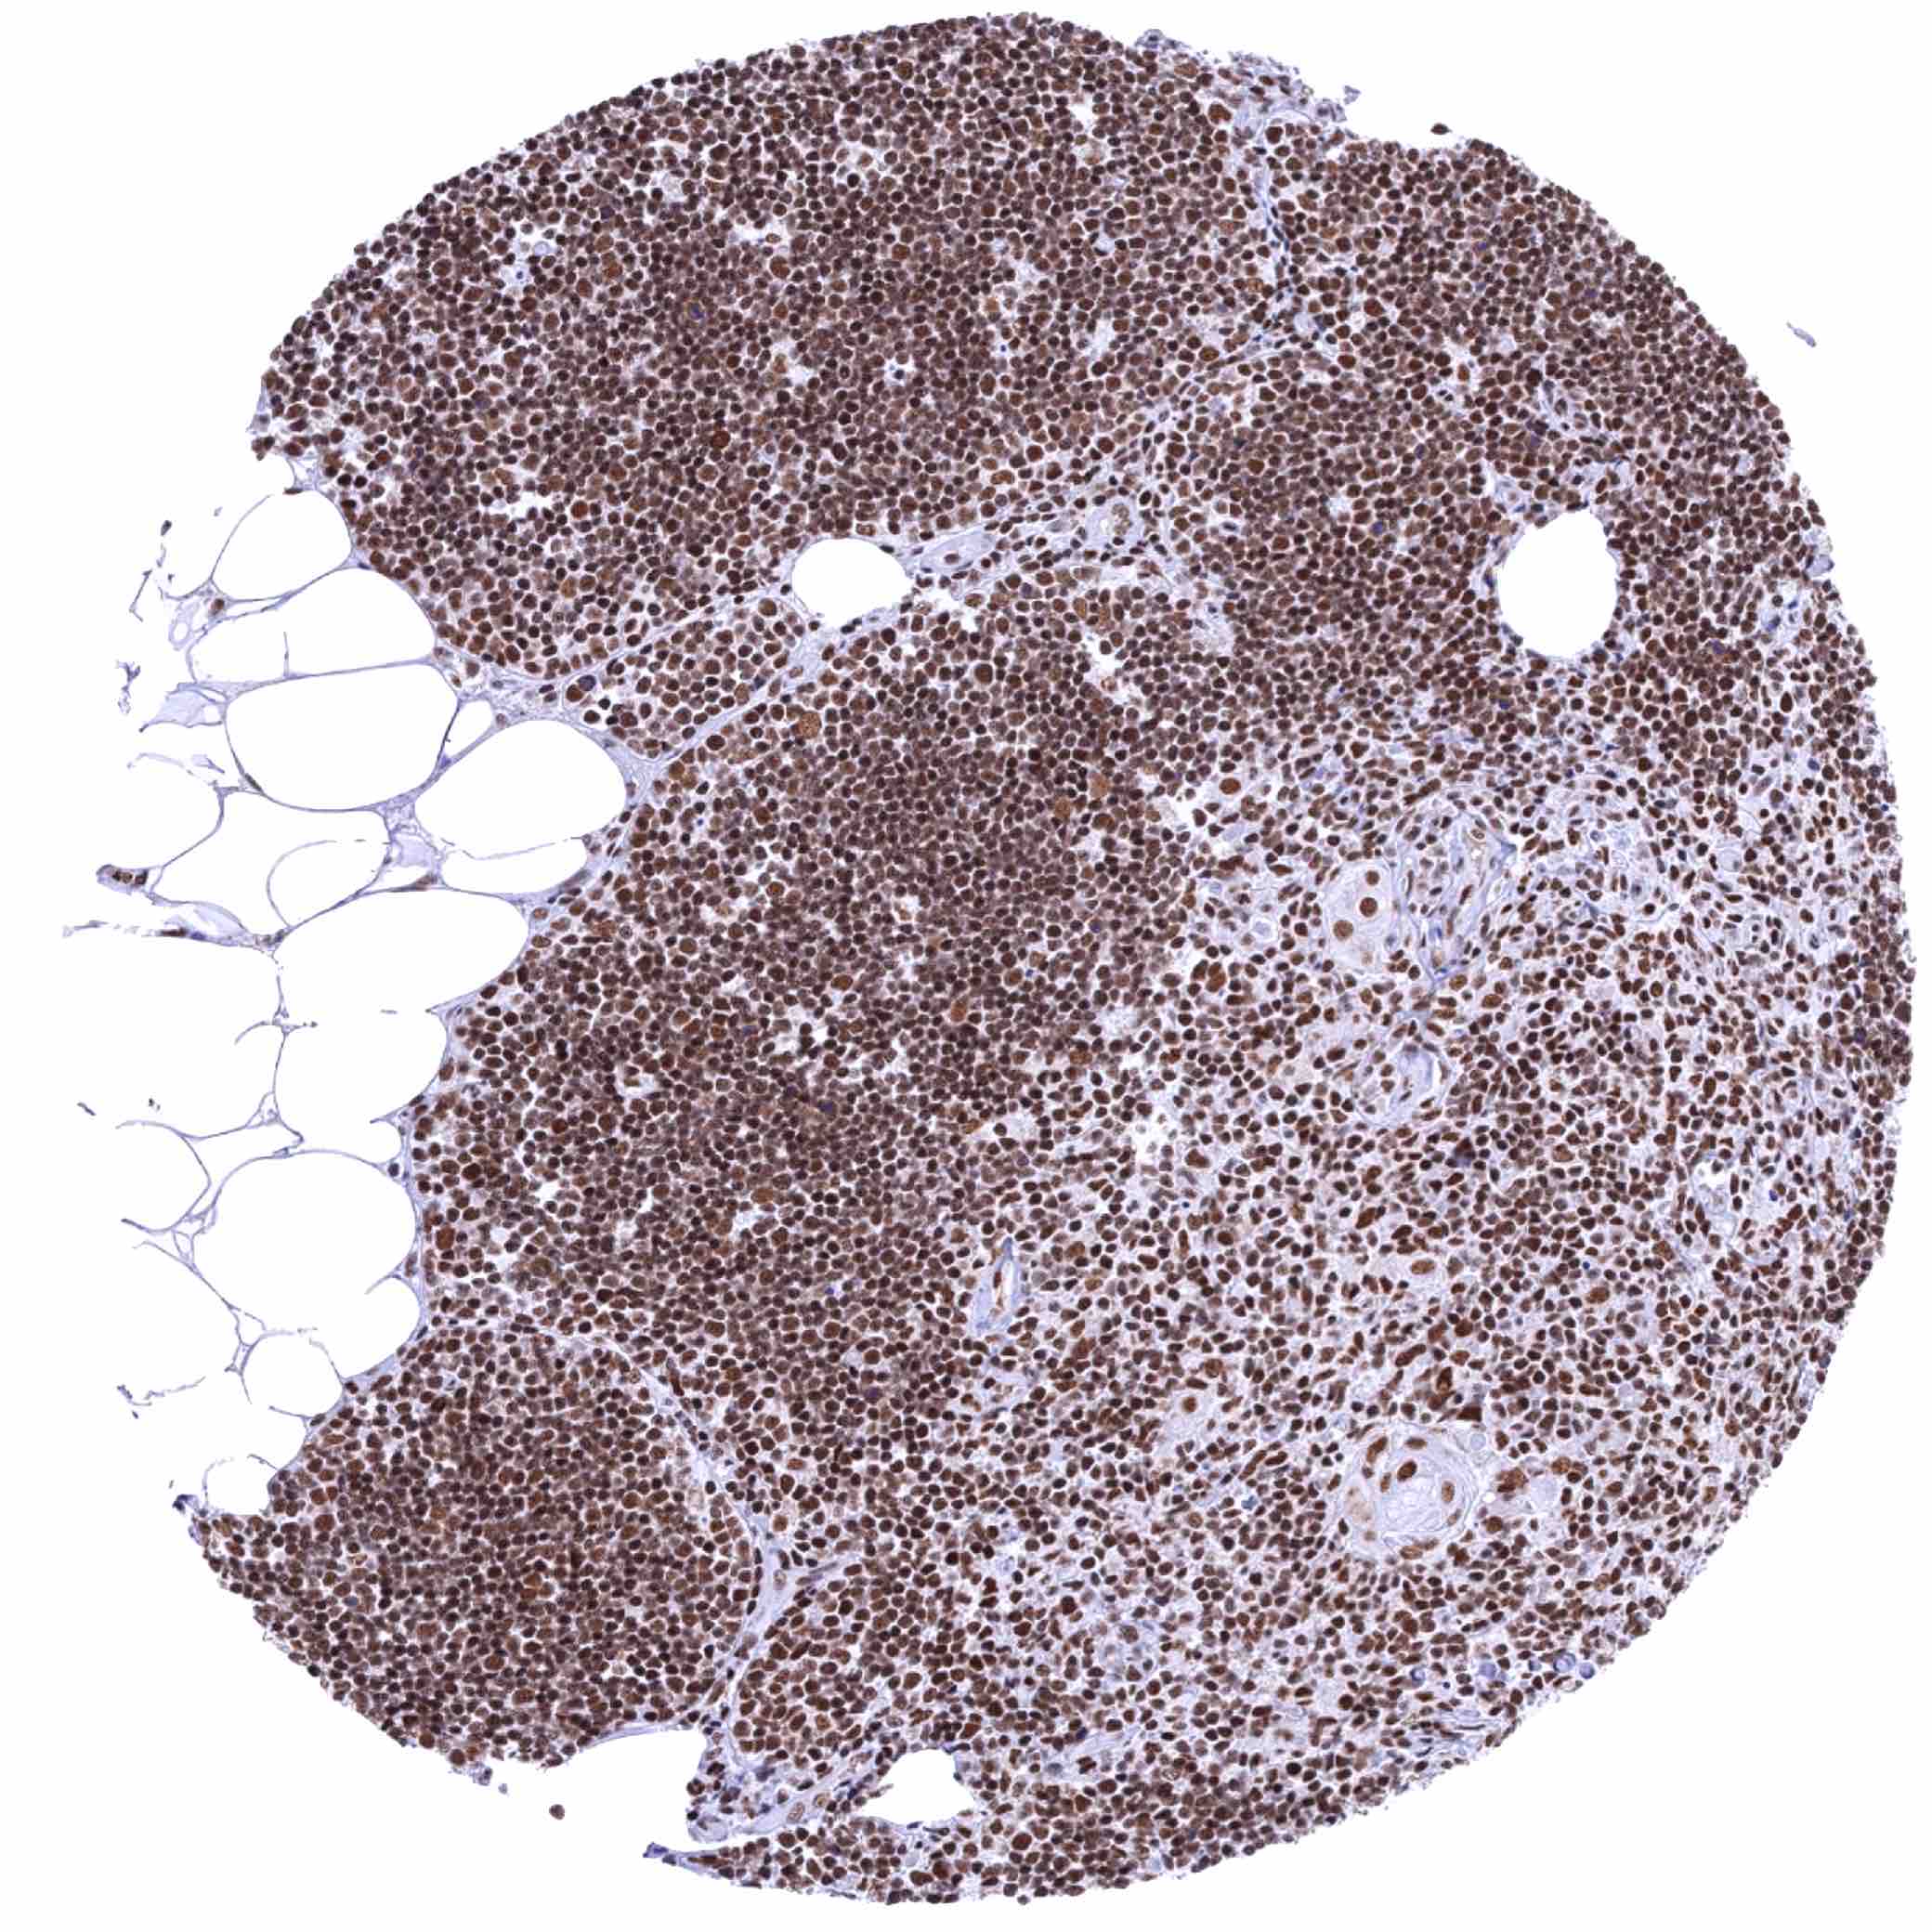

Thymus – Intense nuclear KDM6A staining of all cell types